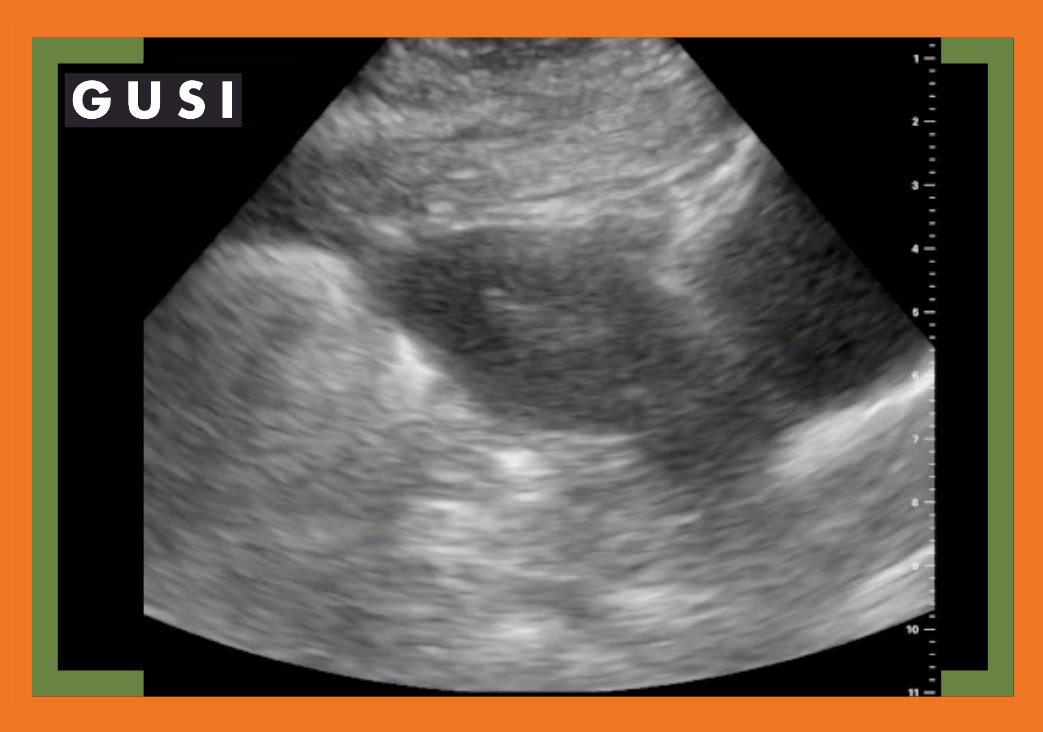

Check out our video and share your thoughts on this case study. Also, be sure to read our diagnosis here👇

globalultrasoundinstitute.com/a-point-of-car…

#pocus #Ultrasound #MedicalEducation #MedEd #pocusEducation #familymedicine #askpocus #MedTwitter @askpocus @POCUS_Society @ubcpocus @DRsonosRD